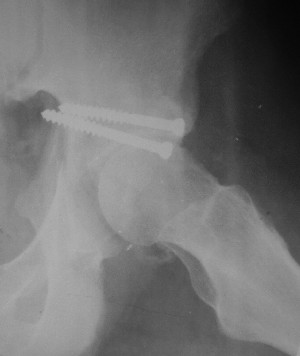

Послеоперационный снимок боковой 5/06/03

Больной 18 мая 2003 года в автоаварии получил перелом левой вертлужной впадины, вывих бедра. Госпитализирован в один из стационаров области.Вывих вправлен. В последствии бедро вывихивалось еще дважды. На консультацию был представлен снимок от 19.05.03г., больной переведен к нам 3.06.03г. Снимок при поступлении - перелом впадины, задне-верхний вывих бедра. 05.06.2003 г. выполнено открытое вправление вывиха левого бедра и остеосинтез стенки вертлужной впадины двумя винтами. Послеоперационный период без осложнений. Объем движений в левом тазобедренном суставе восстановился полностью. Выписан на амбулаторное лечение в удовлетворительном состоянии с рекомендациями 3 месяца ходить на костылях без нагрузки на оперированную конечность. На контрольных рентгенограммах левого тазобедренного сустава 13.10.2003 г. - признаки консолидации перелома; плотность, форма головки и состояние суставных поверхностей удовлетворительные. Разрешена дозированная осевая нагрузка, на конечность с использованием дополнительной опоры. 19.12.2003 г. больной обратился с жалобами на боли в левом тазобедренном суставе. На рентгенограммах левого тазобедренного сустава 19.12.2003 г., 20.02.04г. - асептичекий некроз головки бедра. 5.04.04г. - эндопротез. Сейчас ходит без трости, не хромает. Особенность эндопротезирования - при удалении винтов прослежена линия перелома заднего края впадины и предложено установить чашку несколько меньшего диаметра, чтобы она была покрыта несломанной частью.